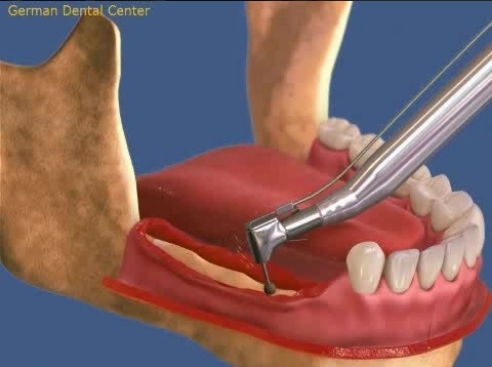

- Имплантация